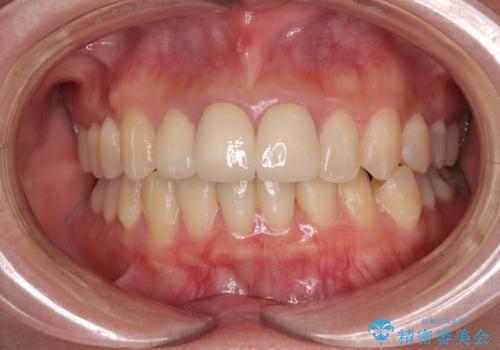

前歯の黒い縁を綺麗にしたい 前歯のオールセラミック

- 以前に装着した前歯のクラウンの縁が見えていることを気にして来院された患者様です。

金属を除去したことで、周りと調和した自然な色合いとなり、クラウンの際の位置も歯肉に少し入り込む位置となっているためまるで本物の歯のような仕上がりとなりました。